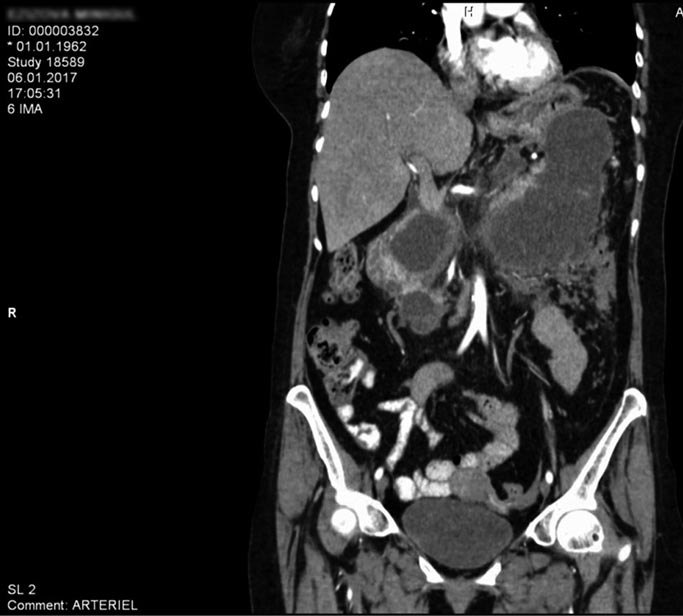

Методы визуализации при ХП. КТ считают лучшим методом для первичной визуализации при обследовании по поводу ХП [19]. Преимущества КТ заключаются в том, что она широкодоступна, демонстрирует подробный обзор изменений морфологии поджелудочной железы, возникающих при ХП, и особенно полезна для выявления изменений, наблюдаемых при осложнениях болезни. КТ быстро оценивает патологию соседних органов, внося ясность в отношении различных проявлений, имитирующих ХП. Ещё одно преимущество КТ — её способность обнаруживать различные осложнения острого панкреатита и ХП, такие как псевдокисты (рис. 1), непроходимость жёлчных путей или двенадцатиперстной кишки, венозный тромбоз, псевдоаневризмы и панкреатико-плевральные свищи [9].

Рис. 1. Визуализация псевдокисты поджелудочной железы на компьютерной томограмме [9]